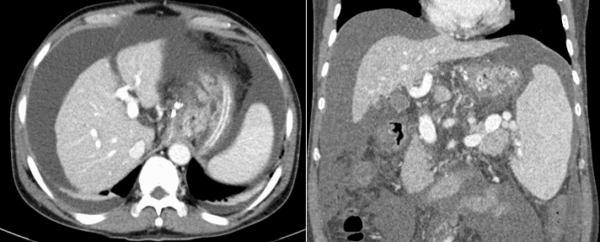

Kỹ thuật TIPS trên một ca bệnh chảy máu do giãn tĩnh mạch dạ dày - Ảnh BVCC

Sau khoảng 1 giờ can thiệp, các bác sĩ đã đặt một stent phủ vào trong gan, làm giảm áp lực tĩnh mạch cửa và nút tắc hoàn toàn các búi giãn tĩnh mạch thực quản.

Ê-kíp của Tiến sĩ Trần Quang Lục đã can thiệp cho người bệnh bằng kỹ thuật TIPS với sự hỗ trợ của hệ thống máy chụp mạch số hóa xóa nền DSA và các trang thiết bị hiện đại. Toàn bộ quy trình kỹ thuật được thực hiện trong lòng mạch máu với một vết chọc rất nhỏ tạo đường vào ở tĩnh mạch cổ.